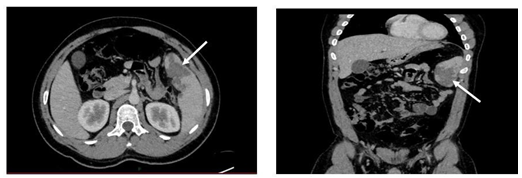

La ecografía abdominal reveló discreta esplenomegalia con alteración de su ecogenicidad que sugería infartos subcapsulares esplénicos. Estos hallazgos se confirmaron con tomografía (figuras 1 y 2). Se descartó endocarditis infecciosa, trombosis venosa esplénica, microangiopatía trombótica, cardioembolia, trombofilia heredada, neoplasia y malignidad hematológica.

Figuras 1-2  Tomografía axial computarizada. La flecha blanca indica área que corresponde a infarto esplénico.